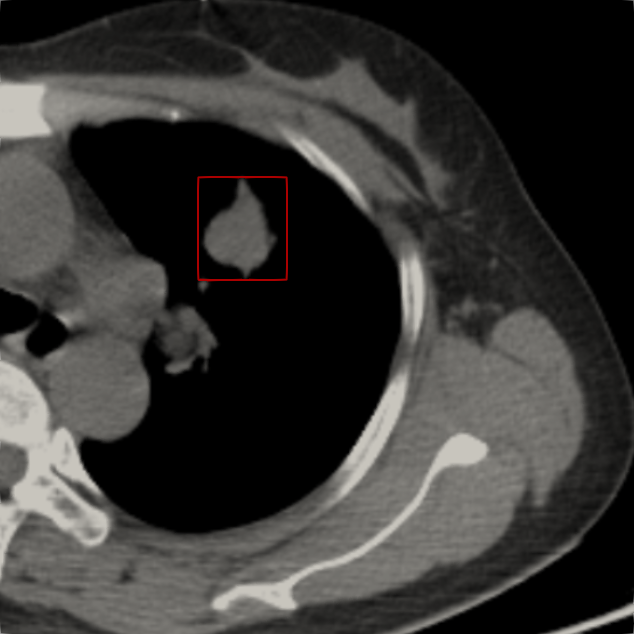

7.3. Beam in 2D patient CT

Having validated the CSD solvers against StarMAP and a Monte Carlo framework in section 7.1, we now examine a realistic 2D CT scan of a lung patient as a proof of concept for the application of our framework to radiation therapy computations. The patient data was retrieved from an open source data set (Li et al., 2020) in The Cancer Imaging Archive (TCIA) (Clark et al., 2013). The patient is irradiated with an electron beam of MeV. We model this beam as the initial condition

where is the beam position within the domain and is the beam direction. The remaining parameters are chosen as . To determine a tissue density for given gray-scale values of the CT image, we set the maximum density, represented by white pixels, to the density of bone . The remaining tissue is scaled such that the minimum pixel value of zero corresponds to a minimal density of . This corresponds approximately to the lower bound of observed lung densities (Kohda and Shigematsu, 1989).